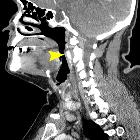

Kissing

carotids: a lovely term for an anatomic variant with great clinical significance. Sagittal reconstructed image showing the retropharyngeal course of the right internal carotid artery (arrowhead).